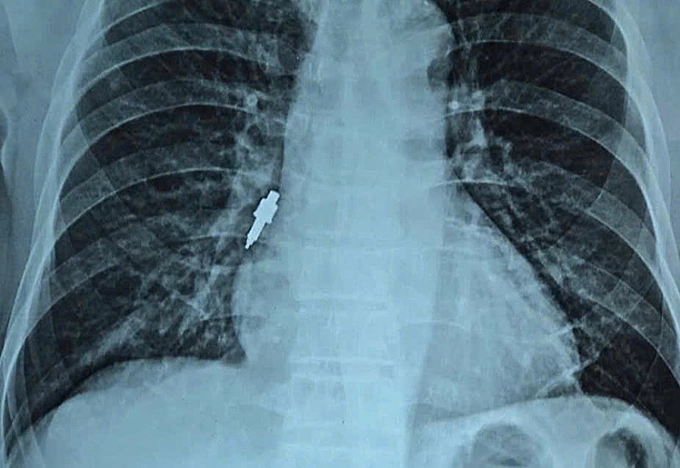

Hà Nội- Sau hai tuần cấy ghép implant tại phòng khám tư, người đàn ông 78 tuổi ho dữ dội, bác sĩ Bệnh viện Hữu Nghị phát hiện một dụng cụ kim loại kẹt sâu trong phế quản.